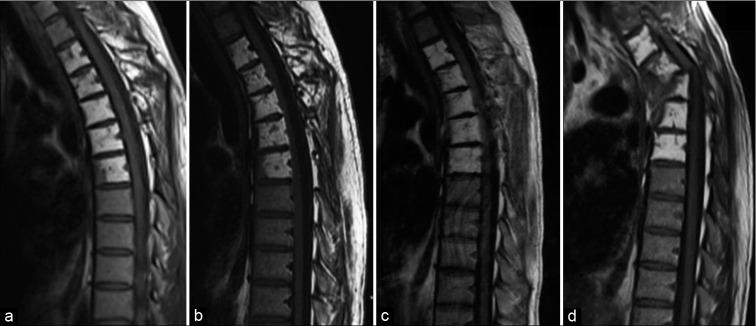

A 25-year-old male with GSD involving the T2 to T6 levels presented with acute traumatic kyphoscoliosis at T3 and T4 and left lower extremity paraparesis. The CT scan 4 weeks before this showed progressing osteolysis versus the CT 5 years ago. Unfortunately, the patient underwent delayed treatment resulting in permanent neurological sequelae. Surgery included a laminectomy and vertebrectomy of T3/T4 with instrumented fusion from T1-10. The use of the spinal instability neoplastic score (SINS) is a useful tool to prompt early referral to spine surgeons.

一名25岁男性,GSD累及T2至T6节段,出现T3和T4水平的急性创伤性脊柱侧凸和左下肢轻瘫。此次检查前4周的CT扫描显示骨质溶解进展,与5年前的CT相比。不幸的是,患者接受了延迟治疗,导致永久性神经后遗症。手术包括T3/T4椎板切除术和椎体切除术,并进行T1-10节段的器械融合。使用脊柱不稳定肿瘤评分(SINS)是促使早期转诊至脊柱外科医生的有用工具。